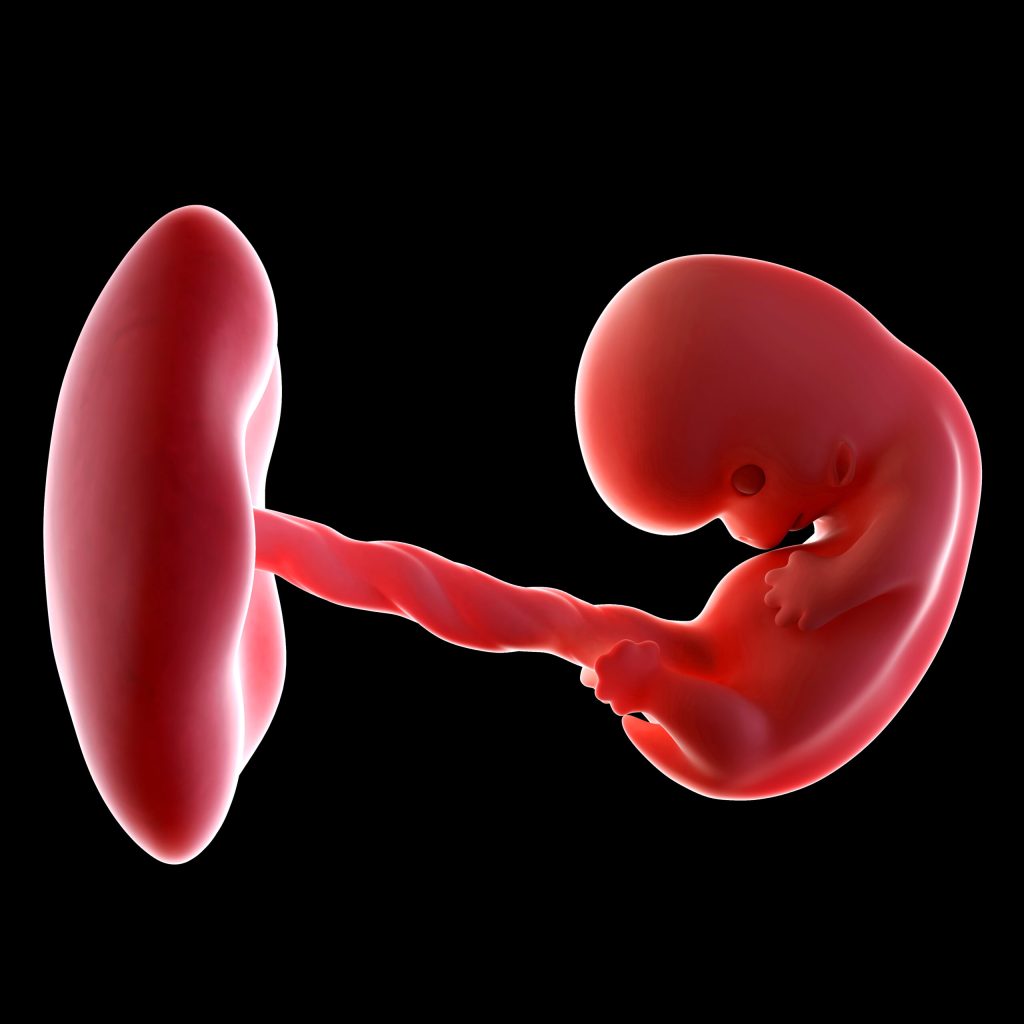

Vanaf een zwangerschapsduur van 4 weken is er rondom het hoopje cellen (de blastocyste) een vruchtzakje ontstaan. Vanaf dan spreek je van een embryo. Terwijl het misschien voelt alsof het allemaal nog moet gaan beginnen, is er al veel gebeurd daar binnen in je lichaam. En de ontwikkeling gaat op hoog tempo door. In deze week is het embryo weliswaar nog maar een paar millimeter groot, maar het bestaat dan al uit maar liefst 125.000 cellen! De zwangerschap is volledig ingenesteld in het baarmoederslijmvlies. Qua vorm lijkt het wel een piepklein kikkervisje. Het ronde deel zal uiteindelijk het hoofdje worden en het staartdeel van het ‘kikkervisje’ groeit uiteindelijk uit tot het lichaam. Voorheen deelden de cellen zich allemaal hetzelfde, maar vanaf nu gaat dit veranderen. Het embryo bestaat uit drie lagen, waarbij elke laag zich op een andere manier zal gaan ontwikkelen. Dit gebeurt door zogenaamde ‘inductie’, waarbij het ene weefsel het andere weefsel aanzet tot ontwikkeling en dat alles in een logische volgorde. Bizar toch? Het is een belangrijk proces, want verstoringen in deze ontwikkeling zouden kunnen leiden tot een miskraam of aangeboren afwijkingen.

De aanleg van de placenta begint nu ook al. Dit gebeurt op de plek waar het embryo aan de baarmoederwand vastzit. Je kan je voorstellen dat het een zeer belangrijke periode is voor de ontwikkeling van je kindje.

In deze periode maakt het embryo nog gebruik van een zogenaamde voedingsvoorraad uit de dooierzak. Het dooierzakje is zo’n twee weken na de bevruchting al ontstaan en groeit vervolgens door. Naast het voorzien in voedingsvoorraad voor het embryo maakt de dooierzak zwangerschapshormoon aan, waardoor er niet opnieuw een eisprong zal plaatsvinden en waardoor het opgebouwde baarmoederslijmvlies intact blijft. Als je 5 weken zwanger bent kan je het dooierzakje zien op de echo. Het is op dat moment groter dan het embryo zelf. Op de echo zie je het dooierzakje terug als een ringetje, dat samen met het embryo in de vruchtzak ligt. Je kan het dooierzakje zien als een soort knapzakje met extra’s voor de eerste embryonale fase. Zodra de placenta helemaal is aangelegd en volledig functioneert vervalt de functie van de dooierzak, maar dit zal nog een aantal weken duren.

Bij 5 weken zijn de armpjes en beentjes al zichtbaar als kleine bobbeltjes. De ruggengraat, hersenen en huid beginnen zich te vormen. Week 5 is cruciaal voor de aanleg van het hart. Zo’n 16 dagen na de bevruchting begint het hart zich te vormen. Wist je eigenlijk dat het hart begint als één enkele buis? Pas hierna vormt het zich door verschillende afsnoeringen verder. Na 6 tot 8 weken heeft het hart ongeveer zijn definitieve vorm gekregen en zijn ook de hartkleppen gevormd, waarna dit (nog primitieve) hartje begint met kloppen.

Bij deze termijn wordt er een beginnetje gemaakt met de ogen, mond, oren en neus; de ogen zitten dan nog aan de zijkant van het hoofd. Dit klinkt al heel echt, maar je baby lijkt eigenlijk nog een beetje op een mini garnaaltje. In de buik vormen de lever en de nieren zich en er ontstaat een verbinding tussen de mond en de beginnende darmen. Het hartje begint te kloppen met pakweg 65 slagen per minuut en brengt nu ook een bloedsomloop op gang. Vanaf dit punt verhoogt het hart zijn snelheid dagelijks met ongeveer drie slagen per minuut. Dit gaat wel een maand lang zo door. Ook ontstaat de navelstreng, wat betekent dat er nu ook voedingsstoffen en zuurstof vanuit de placenta naar je baby gaan. Koolstofdioxide en afvalstoffen worden afgevoerd. De taak van de dooierzak wordt daardoor kleiner.

Je kindje groeit enorm. Hij of zij is nu wel twee keer zo groot als vorige week! Dat komt voornamelijk door het verder groeien van het hart en hoofd. Het hoofd wordt hierbij in verhouding steeds groter, doordat de hersenen zich razendsnel verder ontwikkelen: iedere minuut worden er zo’n 100 hersencellen geproduceerd! Ook de armen en beentjes beginnen zich te vormen. De beenderen en spieren ontwikkelen, maar bewegen is voor het embryo nog niet mogelijk. De handen zien eruit als een soort zwemvliezen en de ontwikkeling van de voeten laat nog even op zich wachten. De ogen ontwikkelen zich steeds verder. Zo ontstaan de oogleden en wordt de iris gevormd. Diep in de kaak wordt het begin van de melktandjes gemaakt (bizar he?) en ook de luchtpijp wordt gevormd. De longen beginnen te ontwikkelen: dit orgaan ontwikkelt zich nog de gehele zwangerschap door. De placenta functioneert nu volledig en de dooierzak zal gaan verdwijnen